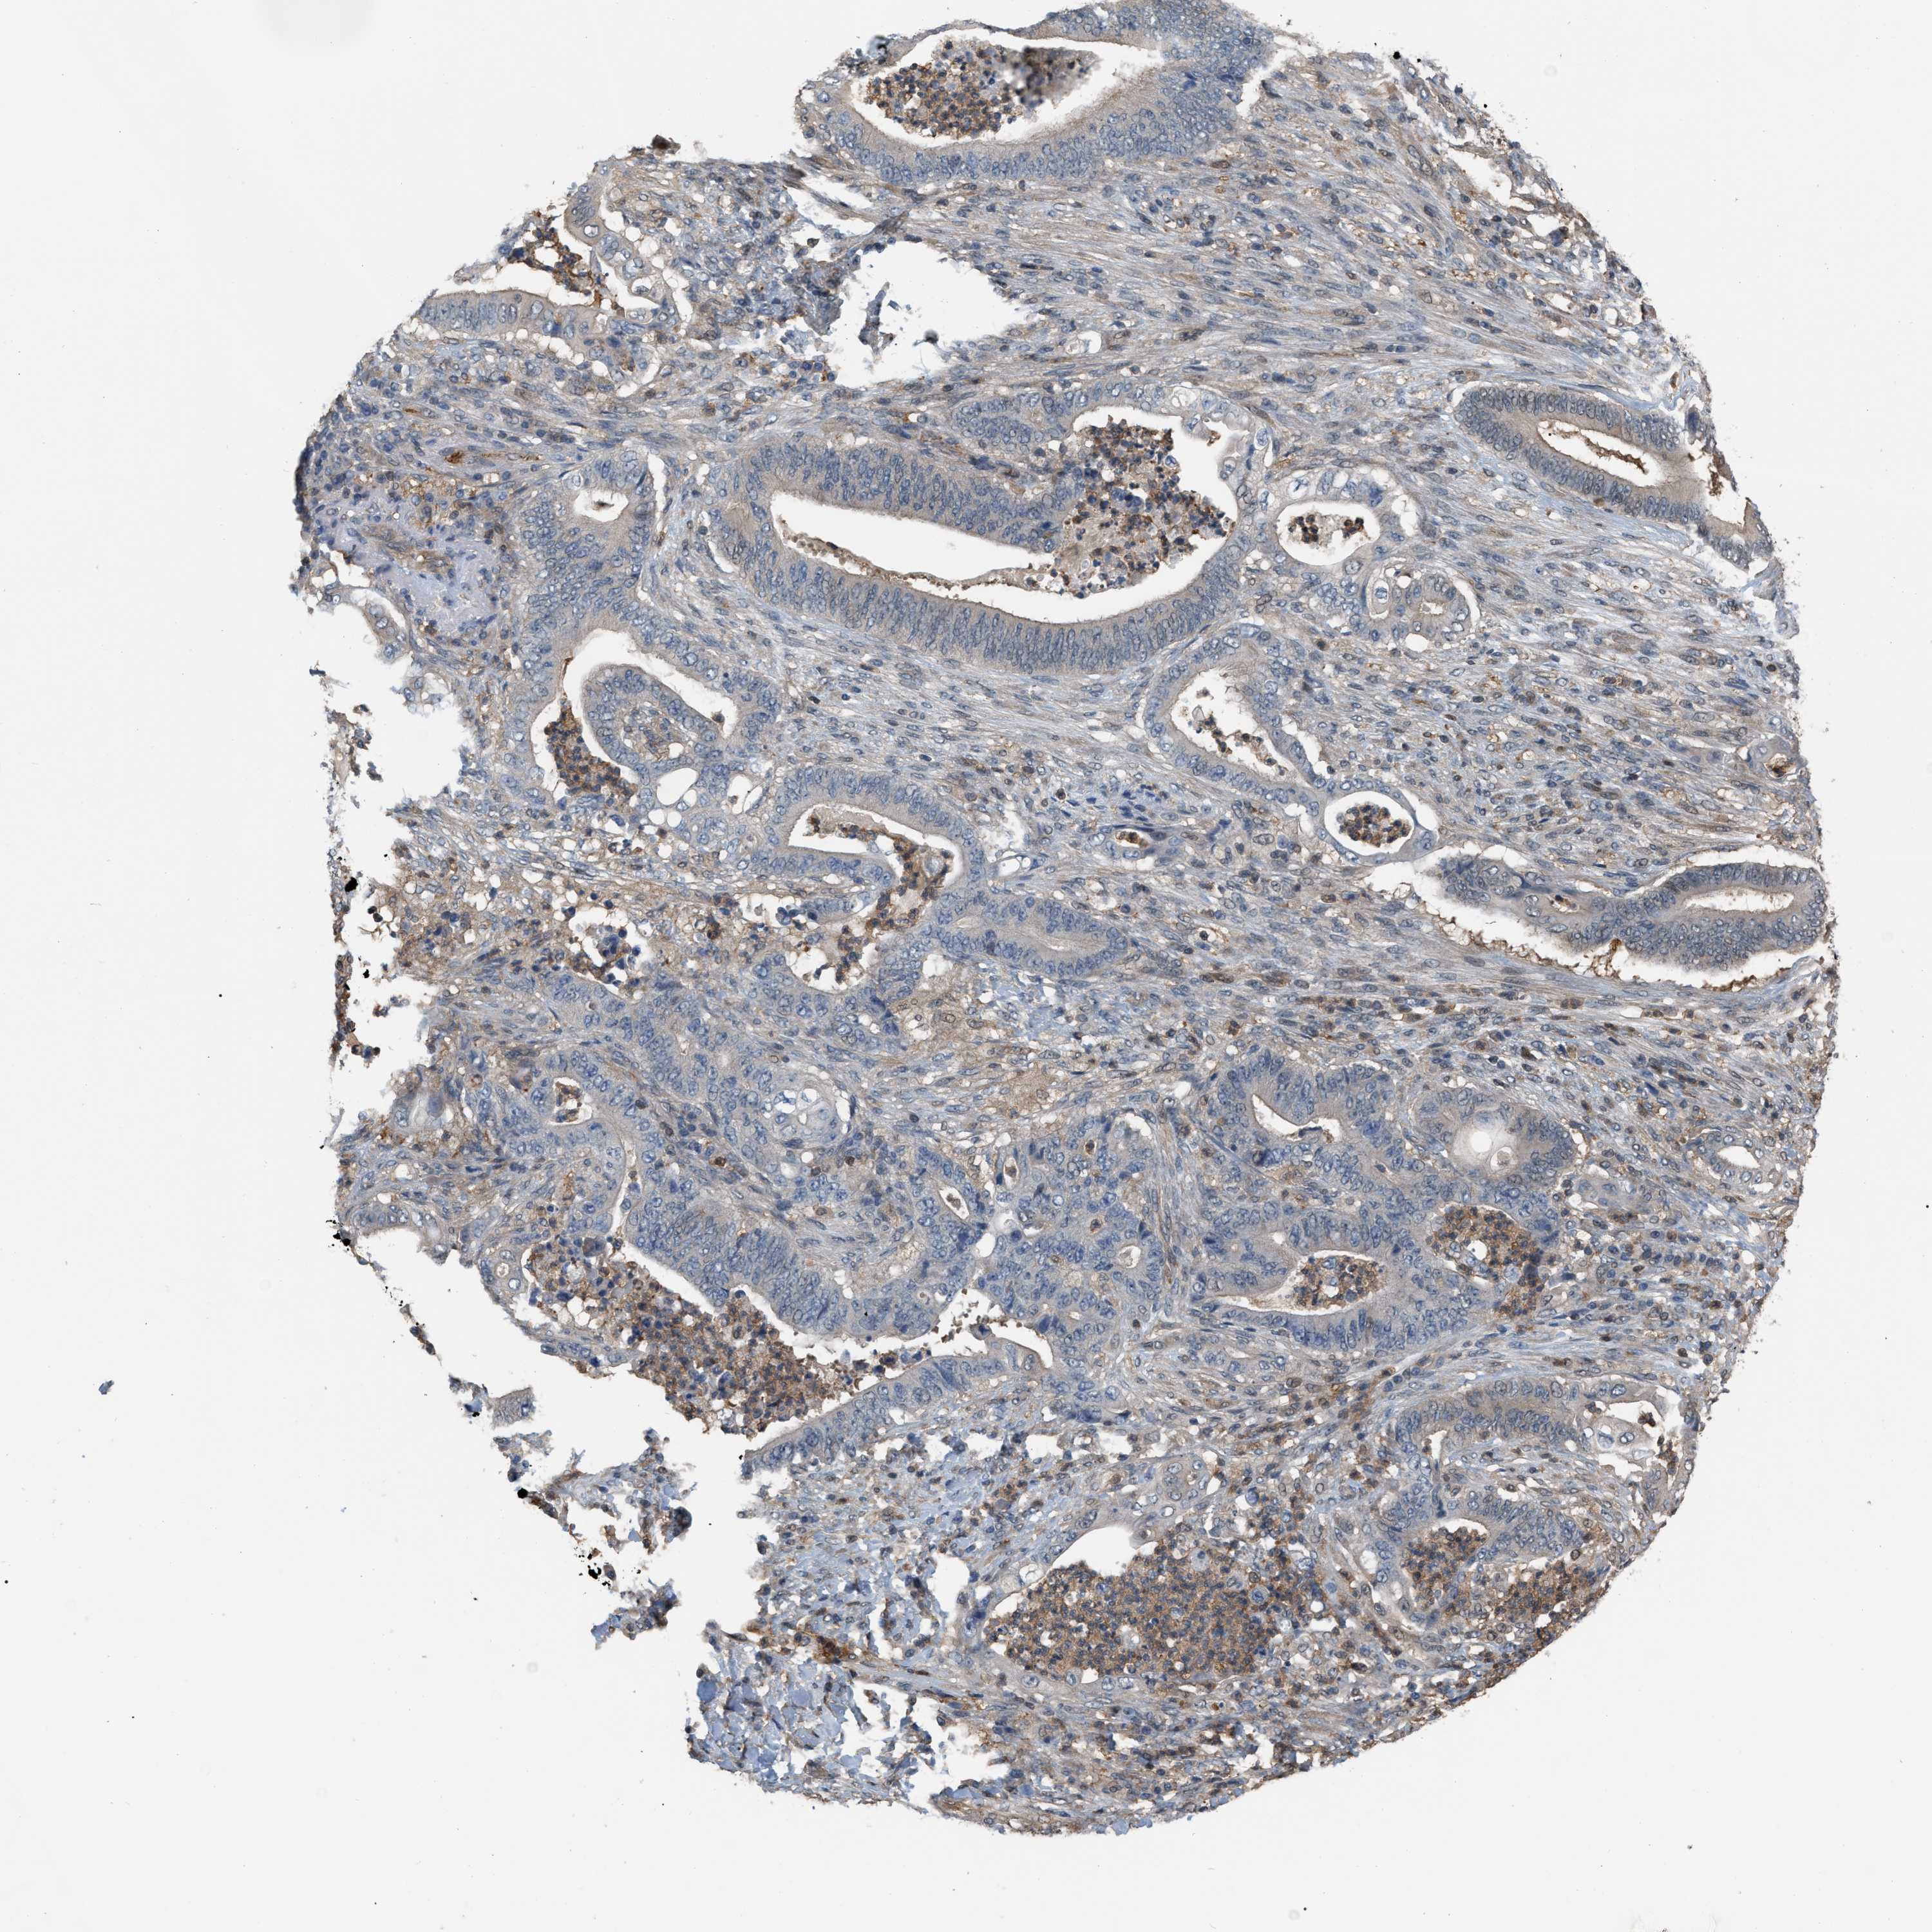

STOMACH CANCER - Protein expressioni

A mouse-over function shows sample information and annotation data. Click on an image to view it in a full screen mode. Samples can be filtered based on level of antibody staining by selecting one or several of the following categories: high, medium, low and not detected. The assay and annotation is described here.

Antibody stainingi

Antibody staining in the annotated cell types in the current human tissue is reported as not detected, low, medium, or high, based on conventional immunohistochemistry profiling in selected tissues. This score is based on the combination of the staining intensity and fraction of stained cells.

Each image is clickable and will lead to virtual microscopy that enables deeper exploration of all samples and also displays staining intensity scores, fraction scores and subcellular localization as well as patient and tissue information for each sample.

Antibody HPA019735

Staining

High

Medium

Low

Not detected

Intensity

Strong

Moderate

Weak

Negative

Quantity

>75%

75%-25%

<25%

None

Location

Nuclear

Cytoplasmic/membranous

Cytoplasmic/membranous,nuclear

Adenocarcinoma, NOS